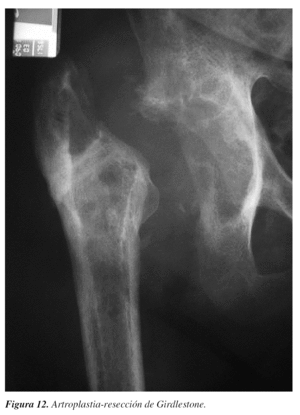

Por último, no hay que olvidar que, aparte de la complicación que supone una luxación recidivante con las consiguientes intervenciones quirúrgicas para estabilizar la cadera, puede sumarse a ella la infección. La asociación de inestabilidad de cadera protésica e infección, desafortunadamente, en ocasiones, acaba en artroplastia-resección de Girdlestone, que probablemente sea de las pocas indicaciones de este tipo de cirugía hoy día (fig. 12).